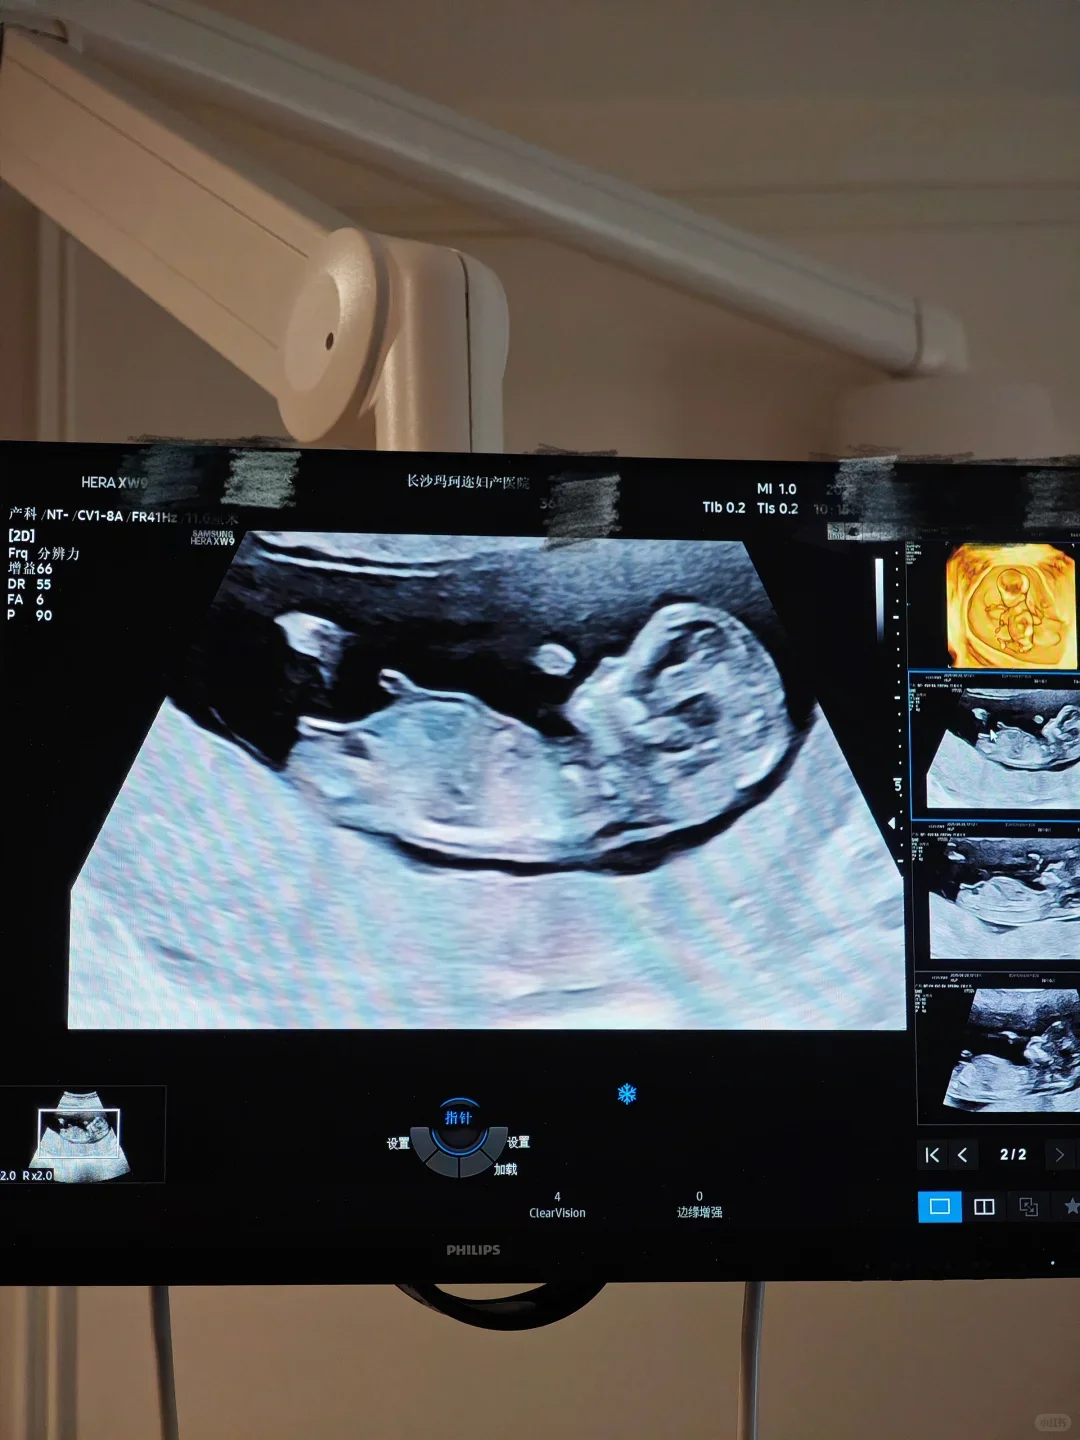

因为很多医院超声结果不互认,我 31 周换到省妇幼的时候,被告知要在她们那里再做一次大排畸。这时候能够约上检查已经很幸运了,超声科的医生也会给做,但是因为宝宝活动空间不足,有些地方很难看清楚。给我做大排畸的医生告诉我,最好在 28 周前做大排畸。

#产检 #四维彩超 #孕晚期